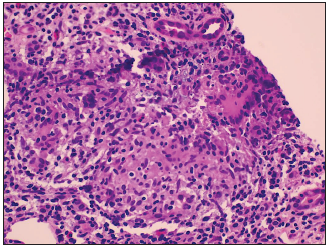

El resultado fue: presencia de 65 glomérulos, 29 con esclerosis global, 2 con esclerosis segmentaria, ausencia de cambios proliferativos glomerulares. En túbulointersticio inflamación ++++ (100%) mononuclear con presencia de histiocitos y formación de granulomas, coloración para bacilos ácido alcohol resistentes negativa, fibrosis intersticial +++ (100%), atrofia tubular +++ (100%), vasos sanguíneos normales, inmunofluorescencia negativa para depósitos, microscopia electrónica presencia de mononucleares en intersticio, concluyéndose nefritis intersticial crónica de tipo granulomatoso (Figura 1). Se descartaron afecciones granulomatosas como tuberculosis y sarcoidosis por medio de estudios complementarios y hallazgos clínicos e imagenológicos.

Figura 1 Hematoxilina y eosina 20x. Presencia de infiltrado inflamatorio intersticial con tendencia a formar granulomas, conformado por células histiocitoides y longitudinales.